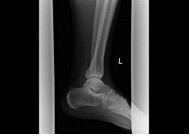

| 膝 | 手関節 | 足関節 |